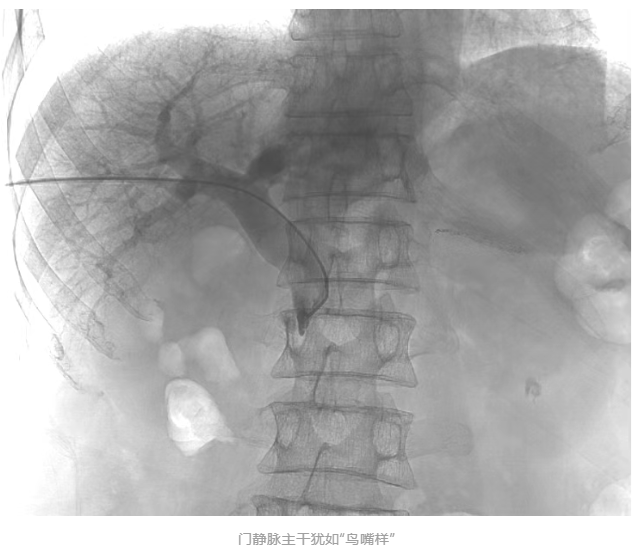

胡育斌主任医师团队在方主亭副院长的指导下开展手术。术中造影显示:肠系膜上静脉完全闭塞,门静脉主干受肿瘤压迫呈“鸟嘴样”狭窄(见下图),血流近乎中断,情况极为严峻。

团队凭借精湛的介入技术和丰富的经验,成功使用黑泥鳅导丝穿越闭塞段,开通肠系膜上静脉。随即,金属支架释放,血管瞬间扩张,造影显示门静脉回流顺畅。与此同时,精准植入碘125粒子条,内照射治疗周边癌细胞以抑制肿瘤继续侵犯血管。